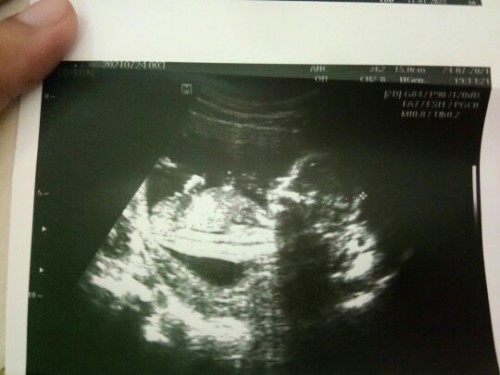

คุณแม่บ้านไหนมีปัญหาเรื่องโรงพยาบาลบ้างคะ บ้านนี้ทางโรงพยาบาลปิดรับการรักษาเกี่ยวกับคนท้อง ส่วนตัวมีสิทธิ์30ที่โรงพยาบาลนั้น แต่ฝากคลินิคค่ะ😟😟